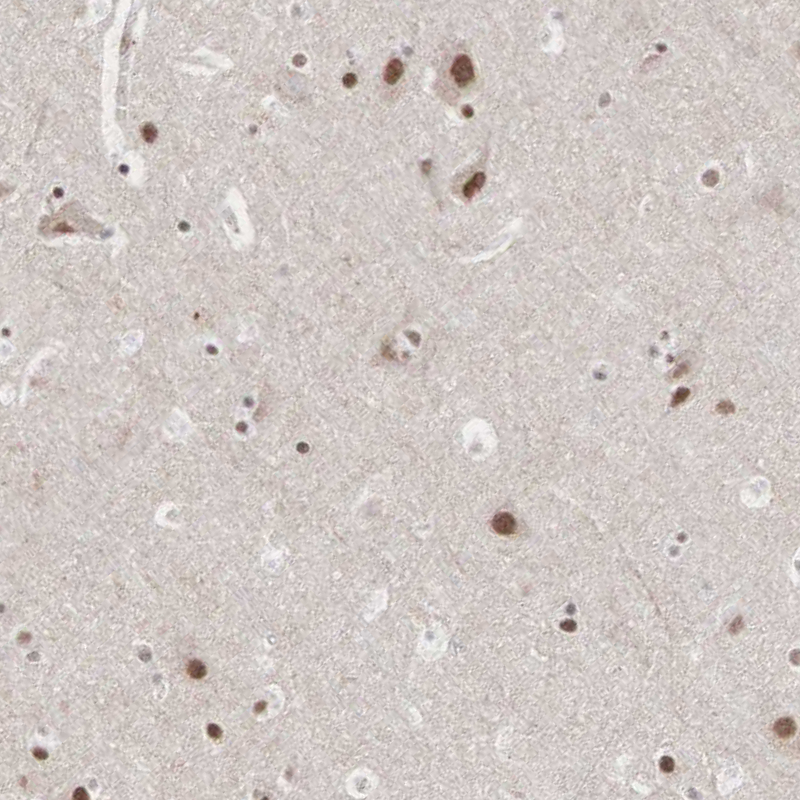

Immunohistochemical staining of human cerebral cortex shows moderate nuclear positivity in neuronal cells.